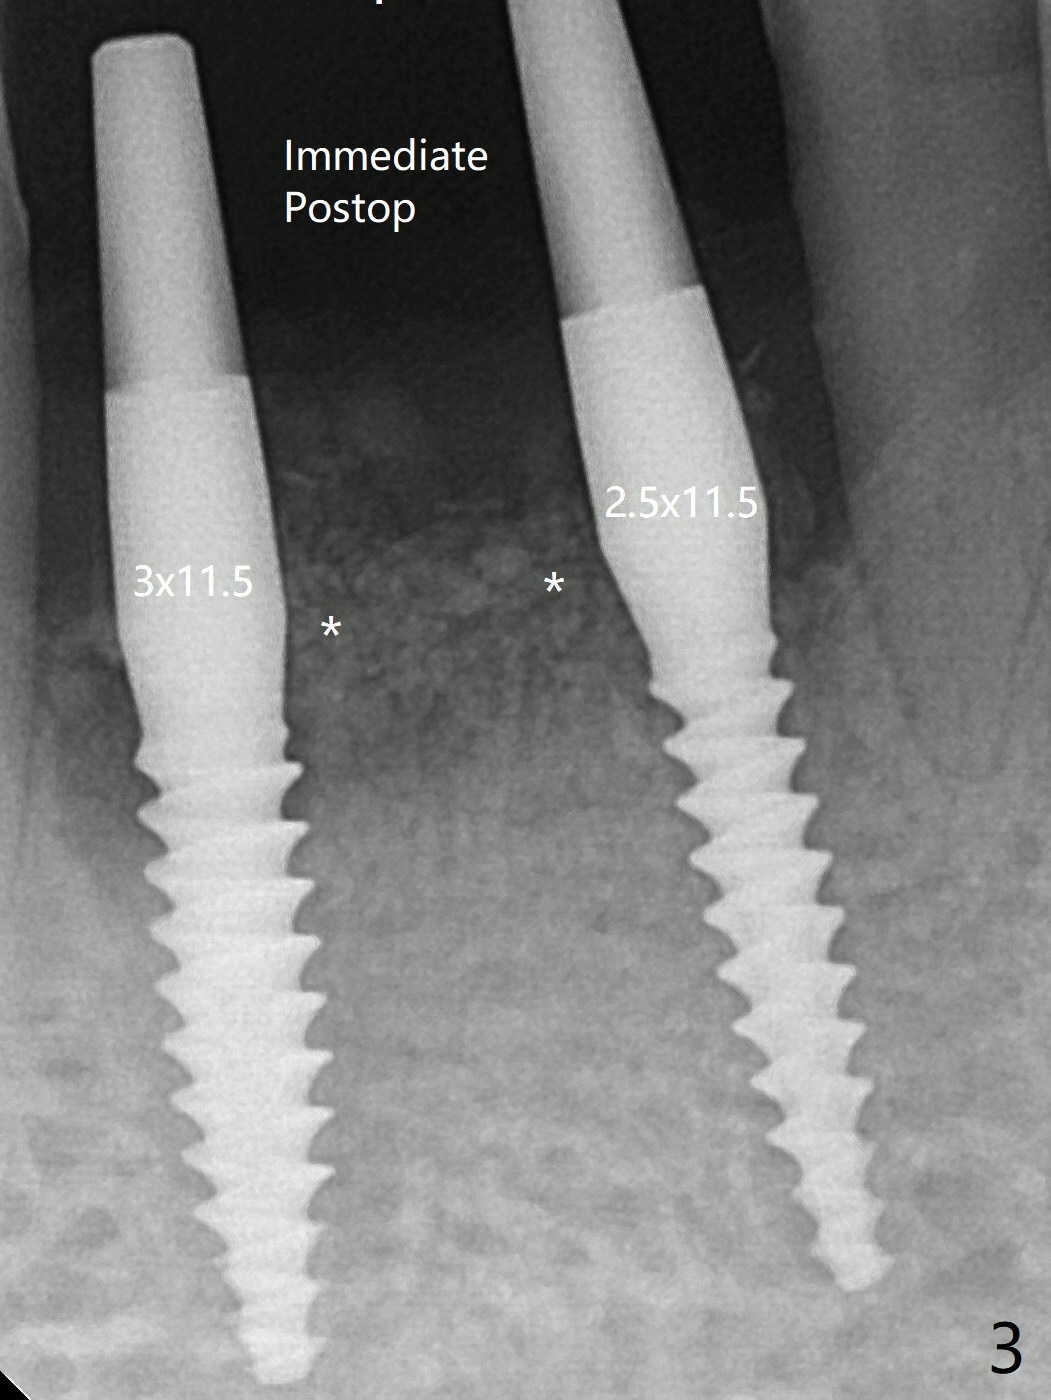

After 2.2 mm drill, a 2.5 mm mini implant is placed at #24 <10 Ncm (Fig.2,3).  Since the ridge at #26 is apparently wider than that of #24 (Fig.1), a 3x11.5 mm implant is placed after the same drill (2.2 mm); insertion torque is ~ 35 Ncm.  Bone graft is placed around the implants (Fig.2,3 *) before placement of PRF membrane.  There is apparently no bone loss 4 months postop with ~ 3 month provisional (Fig.5).  The gingiva is healthy in spite of poor oral hygiene.